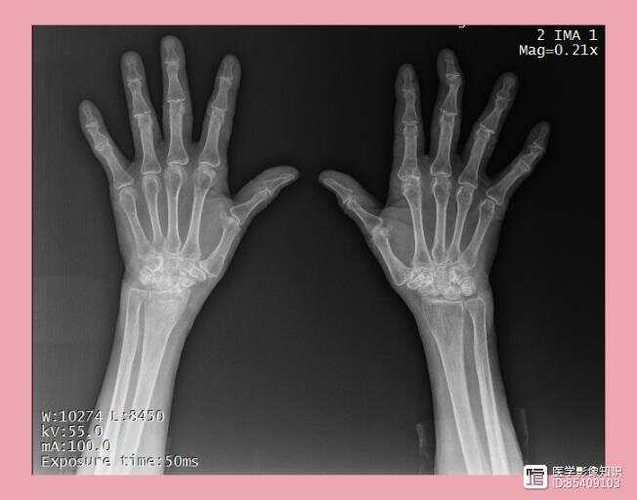

类风湿关节炎的体格检查旨在评估关节的炎症、疼痛、功能损害和畸形,检查应遵循系统性、对称性的原则,因为RA通常是对称性累及多个小关节。

- 特征: RA的肿胀通常是对称性的,呈梭形(手指关节),这是RA的典型特征之一,肿胀是由于关节腔积液、滑膜增生和周围软组织水肿共同造成的。

- 手: 近端指间关节、掌指关节、腕关节。

关节畸形:

(图片来源网络,侵删)- 尺侧偏斜: 手指向小指侧偏斜,是由于掌指关节破坏和内在肌失衡所致。

- 天鹅颈畸形: 近端指间关节过伸,远端指间关节屈曲,形似天鹅的脖子。

- 钮扣花畸形: 远端指间关节过伸,近端指间关节屈曲,形似衣服的纽扣眼。

- “Z”形拇畸形: 拇指的掌指关节过伸,指间关节屈曲。

- “望远镜”手: 由于严重骨质破坏,手指可以像望远镜一样被拉长和缩短。